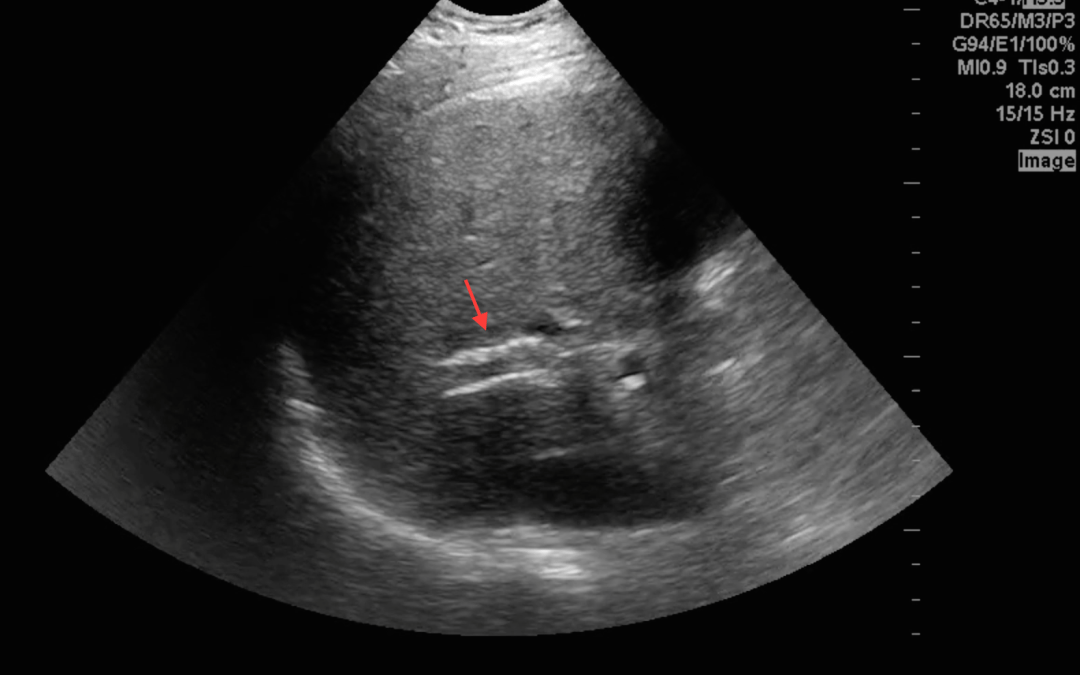

To evaluate the TIPS, the team started by finding the portal vein within the liver. See below.

You can see that the shunt appears hyperechoic compared to what a normal vein would look like. This is because of the synthetic shunt that is in place.